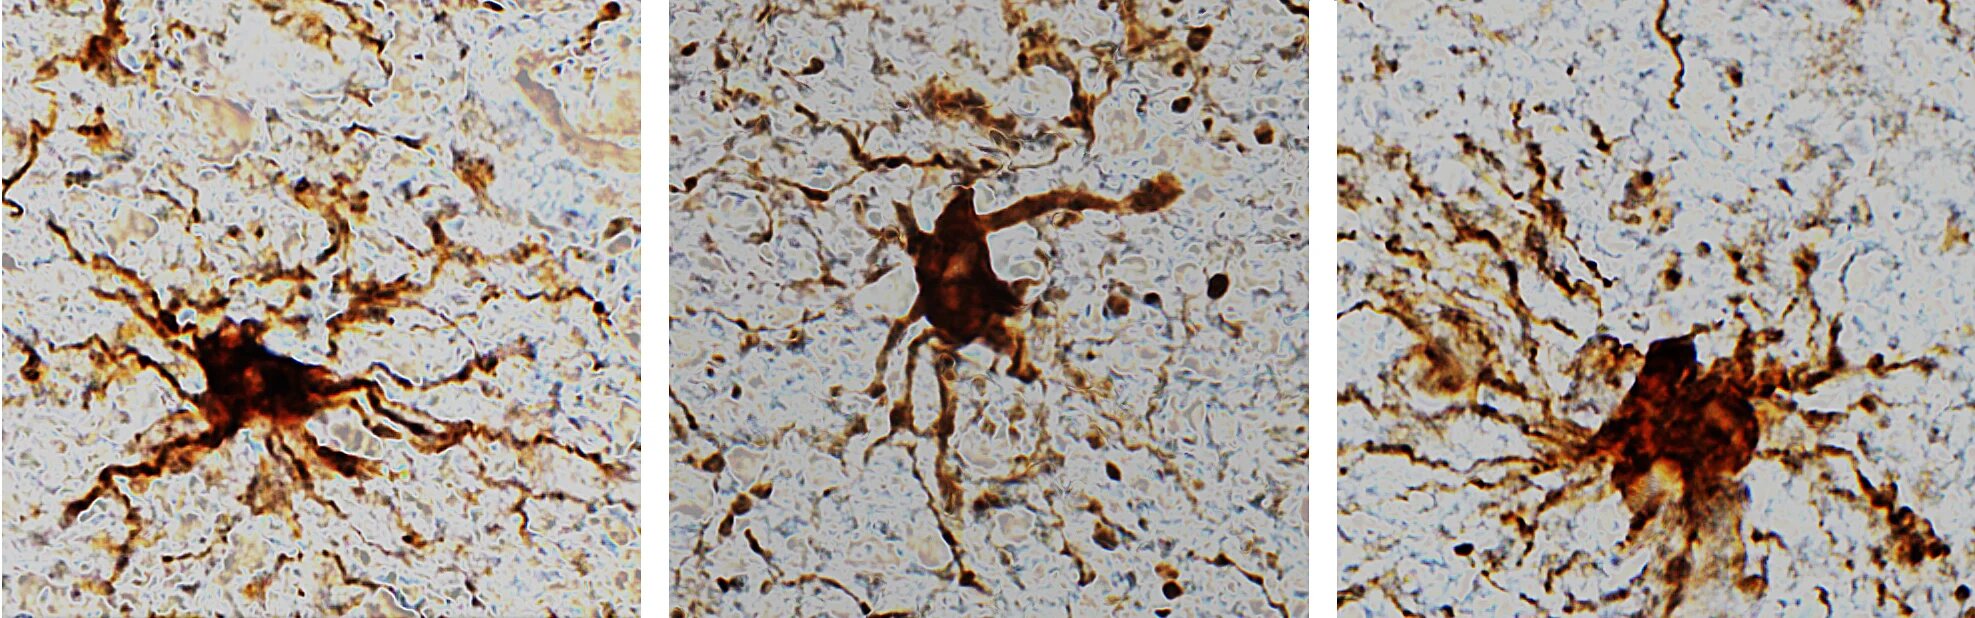

Именно невролог Джеффри Лоуб из Университета Иллинойса и его коллеги заметили, что подобные клетки отращивают длинные придатки и продолжают увлеченно заниматься своими обычными делами в течение еще нескольких часов после смерти.

Ученые изучили результаты гистологии мозговой ткани и заметили, что клеточно-специфическая активность изменяется после смерти человека с течением времени при комнатной температуре.

Исследователи отмечают, что большая часть генов сохраняла активность и оставалась относительно стабильной в течение 24 часов; нейроны и активность их генов истощались довольно быстро. Однако самое примечательное здесь — глиальные клетки, которые активизировались и увеличивали экспрессию генов.

Сначала это кажется просто чем-то непонятным и невероятным, но, на самом деле, здесь скрыт большой смысл, учитывая, что именно глиальные клетки, такие как микроглия и астроциты призываются к действию, когда в организме что-то идёт не так. А что может случиться с организмом хуже смерти?

«Тот факт, что глиальные клетки после смерти активизируются, неудивителен, учитывая, что у них есть противовоспалительная функция, и их работа заключается в очистке головного

При этом через 24 часа эти клетки все-таки умерли, и их уже нельзя было отличить от окружающей их разрушающейся ткани.